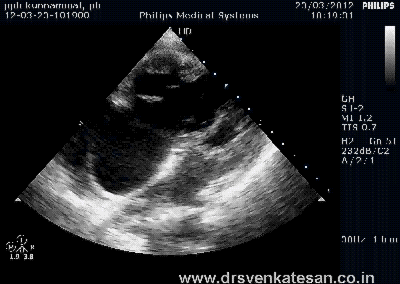

We know RV has a unique shape triangular ( partially pyramidal ) . It can be inferred the RV cavity is formed by fusion of many eccentric spacial planes. We have always believed RV handles the blood it receives from right atrium in a unique way .Now we are beginning to understand it .It is now documented the RV segregates the blood it receives into 4 components.

It is curious to know RV inflow is connected to the outflow by an invisible physiologic Bridge . About 44% of blood traverse the RV in this fashion.

Note : RV blood flow preferentially enters the RVOT with out transiting RV body and apex.Image courtesy http://ajpheart.physiology.org/

After reading this article it seems to me , the mechanical function of RVOT could be most vital. If it fails to handle the first increment which comes directly from RV inflow, stasis is likely in RV body and apex , elevating RVEDP and later promoting stasis leading to clinical events.